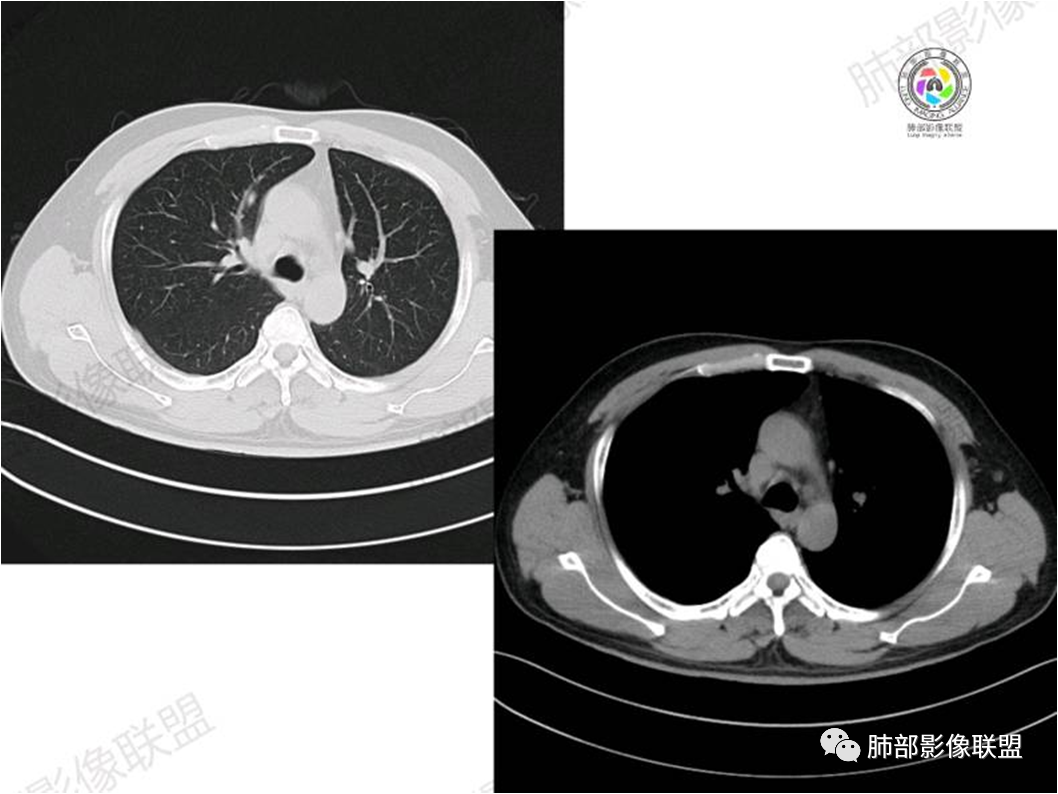

胸部CT:

中年男性,偶有咳嗽,右肺上叶近纵膈旁占位,内可见僵硬的支气管和小空泡征,病灶边缘可见分叶,毛刺,增强病灶中度以上不均匀强化,可见血管造影征,考虑恶性病变,腺癌可能性大。

中年男性,右肺上叶尖段团片病灶,密度均匀,内部支气管充气相,渐进狭窄,强化均匀,血管造影,纵隔侧未见侵犯,诊断:良性,慢性非特异性炎症/机化性炎症,IMT

右肺上叶纵隔胸膜侧一实性肿块,与纵隔胸膜宽基底相连,局部脂肪间隙消失,形态欠规则,内部可见多个小空泡,平扫密度尚均匀,增强后可见点条状强化,内部穿行血管,周围肺组织干净,纵隔淋巴结略肿大,男性44岁,只有咳嗽,考虑恶性肿瘤,腺癌,鳞癌。鉴别结核,OP,炎性假瘤。

右肺上叶近纵膈旁肿块,密度均匀,边缘分叶,毛刺,气管受压变窄,不均匀强化,可见血管造影征,考虑淋巴瘤,鉴别炎性假瘤。

中年男性,右肺上叶纵隔旁软组织肿块,边缘膨隆、毛糙,可见多发分叶,支气管穿行,部分截断,增强后密度欠均匀,纵隔内见多发小淋巴结,首先考虑恶性,腺癌,鉴别淋巴瘤

中年男性,右肺上叶纵隔旁肿瘤,稍膨隆,有毛刺,支气管穿行,远端闭塞,强化均匀,血管走行尚可,考虑淋巴瘤可能性大(支气管远端闭塞,不太符合),鉴别腺癌(气管穿行后闭塞,不太符合),op(病灶稍膨隆)

患者中年男性,咳嗽就诊,无其他不适。胸部CT:右肺上叶尖段上纵膈旁肿块,边界清楚,边缘光滑,内见支气管受压变窄,伴阻塞性改变,增强均匀强化,见血管造影征。综合考虑恶性病变,小细胞肺癌或淋巴瘤。气管镜活检应能明确。

中年男性,右肺上叶纵隔旁实性病灶,边缘有彭隆,有平直,有分叶,有尖角,病灶边缘中心可见支气管征,周围少许磨玻璃,边缘模糊,增强后动脉期病灶可见强化血管影,渐进性强化,临近血管界限清晰。考虑炎性病灶,普通炎性肉芽肿?结核?炎性肌纤维母细胞瘤?鉴别腺癌,淋巴瘤